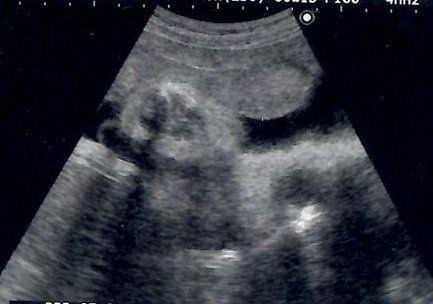

妊娠9週目のエコー写真 胎児の姿が見えてきた!

エコー画像で頭と胴体が分かれた人間らしい姿を見て、いよいよ妊娠したという実感がわいてきました。それと同時に、このまま無事に育ってくれるのだろうかという不安で毎日祈るような気持ちでいました。いまだにこの画像を見るたびに、この時の不安でたまらなかった自分の気持ち、そして生命の神秘を目の当たりにしたときの厳粛な気持ちを思い出し、胸がいっぱいになります。